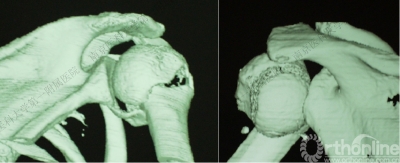

五、反Hill-Sachs 损伤对肩关节稳定性的影响

1.反Hill-Sachs损伤范围对肩关节后方稳定性具有决定性的影响。

2.常规的影像学测量方法不能准确反映损伤范围。

(五)修复反Hill-Sachs损伤

1.外旋肱骨头,显露肱骨头关节面损伤处。

2.改良McLaughlin术、 Underpinning术、球囊扩张术。

3.Dubousset 方法:对肱骨头关节面压缩性骨折均给予直视下复位、填充植骨、螺钉固定,手术指征不受压缩部分占总关节面面积比例的限制。